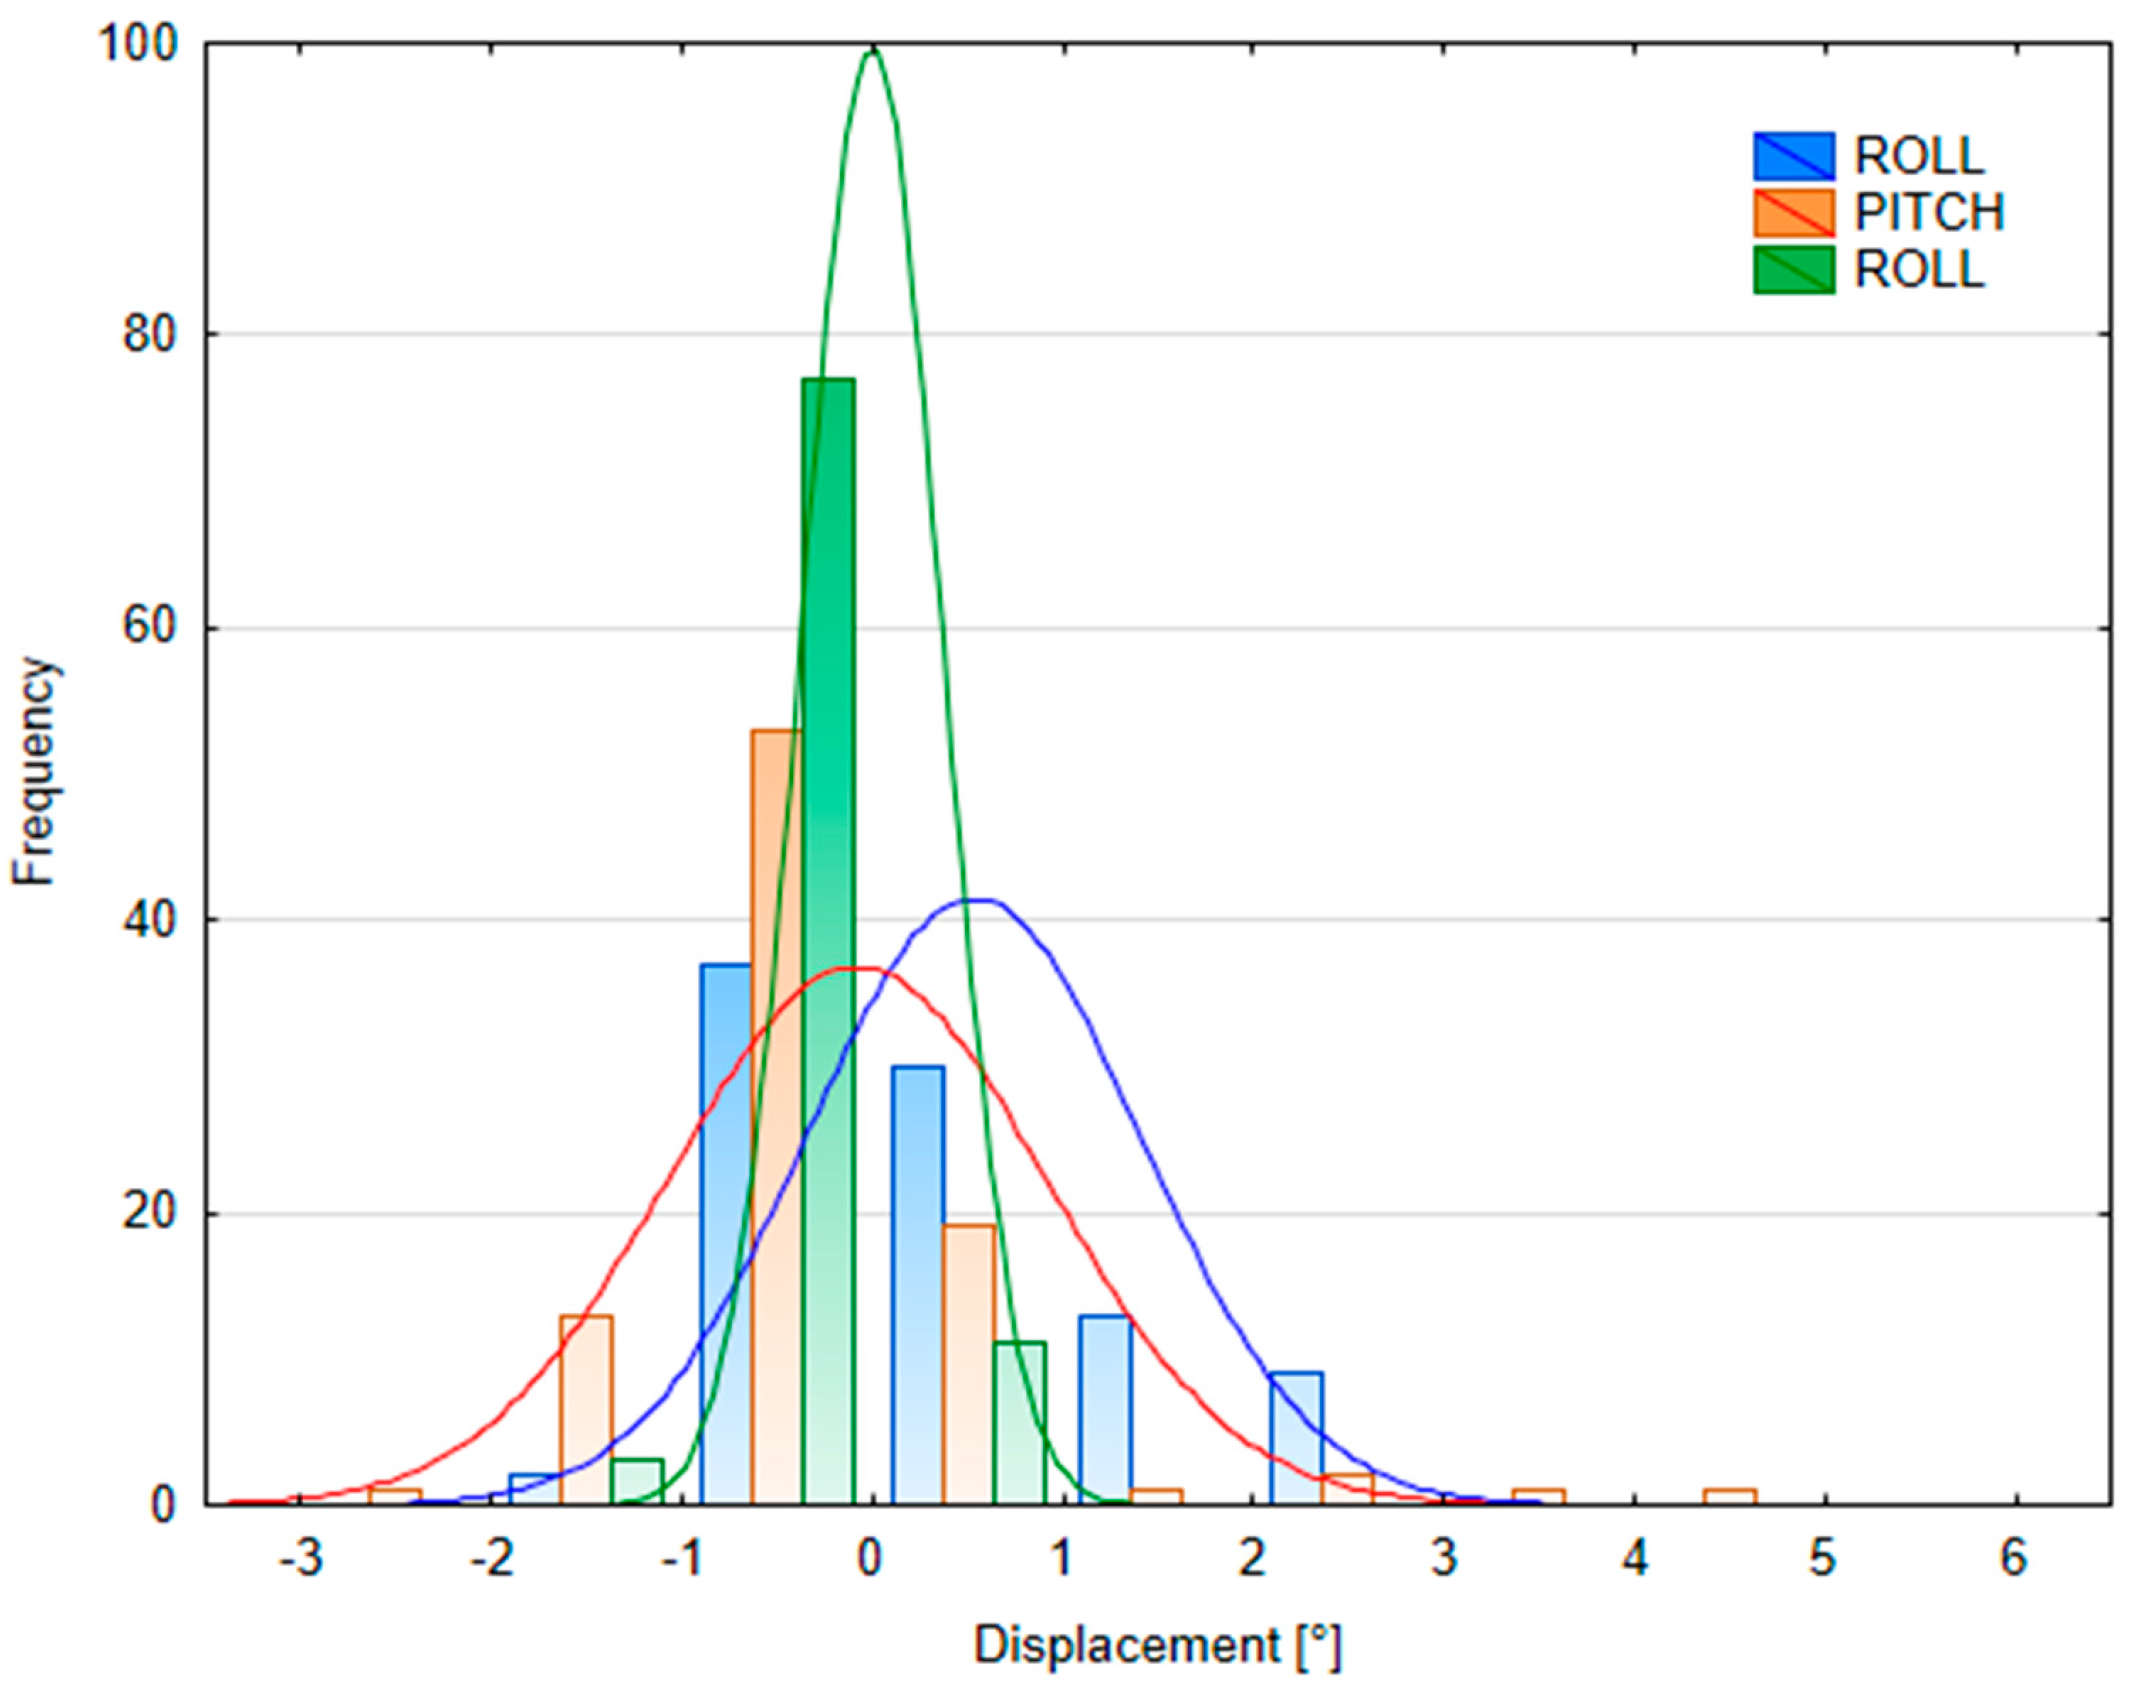

3.2.2. Patient Position Variability

| Table Shift Coordinates | Median SGRT FB Setup Error | Median SGRT DIBH Setup Error | Median SGRT DIBH Reproducibility Error | ||||||

|---|---|---|---|---|---|---|---|---|---|

| Male (n = 58) | Female (n = 46) | p-Value | Male (n = 49) | Female (n = 40) | p-Value | Male (n = 62) | Female (n = 69) | p-Value | |

| X (lateral) [cm] | 0.02 (−0.1; 0.04) | 0 (−0.06; 0.11) | p = 0.06 | −0.08 (−0.14; 0) | 0.08 (−0.03; 0.23) | p < 0.05 | 0 (−0.05; 0.03) | 0.03 (−0.01; 0.08) | p < 0.05 |

| Y (longitudinal) [cm] | 0.03 (−0,07; 0,13) | 0.08 (−0.07; 0.16) | p = 0.27 | −0.24 (−0.54; −0.02) | −0.25 (−0.43; −0.15) | p = 0.72 | 0.02 (−0.12; 0.13) | 0.11 (0.01; 0.19) | p < 0.05 |

| Z (vertical) [cm] | 0.08 (0.01; 0.13) | 0.12 (−0.06; 0.21) | p < 0.05 | −0.1 (−0.2; 0.06) | −0.16 (−0.27; −0.09) | p < 0.05 | 0.07 (−0.02; 0.13) | 0.02 (−0.01; 0.07) | p < 0.05 |

| MAG (magnitude) [cm] | 0.17 (0.14; 0.25) | 0.24 (0.15; 0.29) | p = 0.54 | 0.41 (0.22; 0.68) | 0.40 (0.23; 0.54) | p = 0.38 | 0.19 (0.13; 0.27) | 0.17 (0.12; 0.23) | p = 0.26 |

| ROT [°] | 0 (−0.44; 0.37) | 0.1 (−0.27; 0.53) | p = 0.24 | 0.23 (−0.02; 0.38) | −0.95 (−1.44; −0.12) | p < 0.05 | 0.22 (0.07; 0.35) | 0.03 (−0.19; 0.29) | p < 0.05 |

| PITCH [°] | 0.05 (−0.75; 1.17) | −0.97 (−1.72; −0.23) | p < 0.05 | 0.47 (−0.08; 1.21) | 0.06 (−1.14; 1.23) | p = 0.07 | −0.07 (−0.35; 0.3) | −0.28 (−0.61; 0.02) | p < 0.05 |

| ROLL [°] | 0.18 (−0.26; 0.69) | −0.13 (−0.70; 0.52) | p < 0.05 | −0.04 (−0.17; 0.17) | −0.21 (−0.77; 0.05) | p < 0.05 | 0.05 (−0.06; 0.16) | 0.19 (0.05; 0.28) | p < 0.05 |